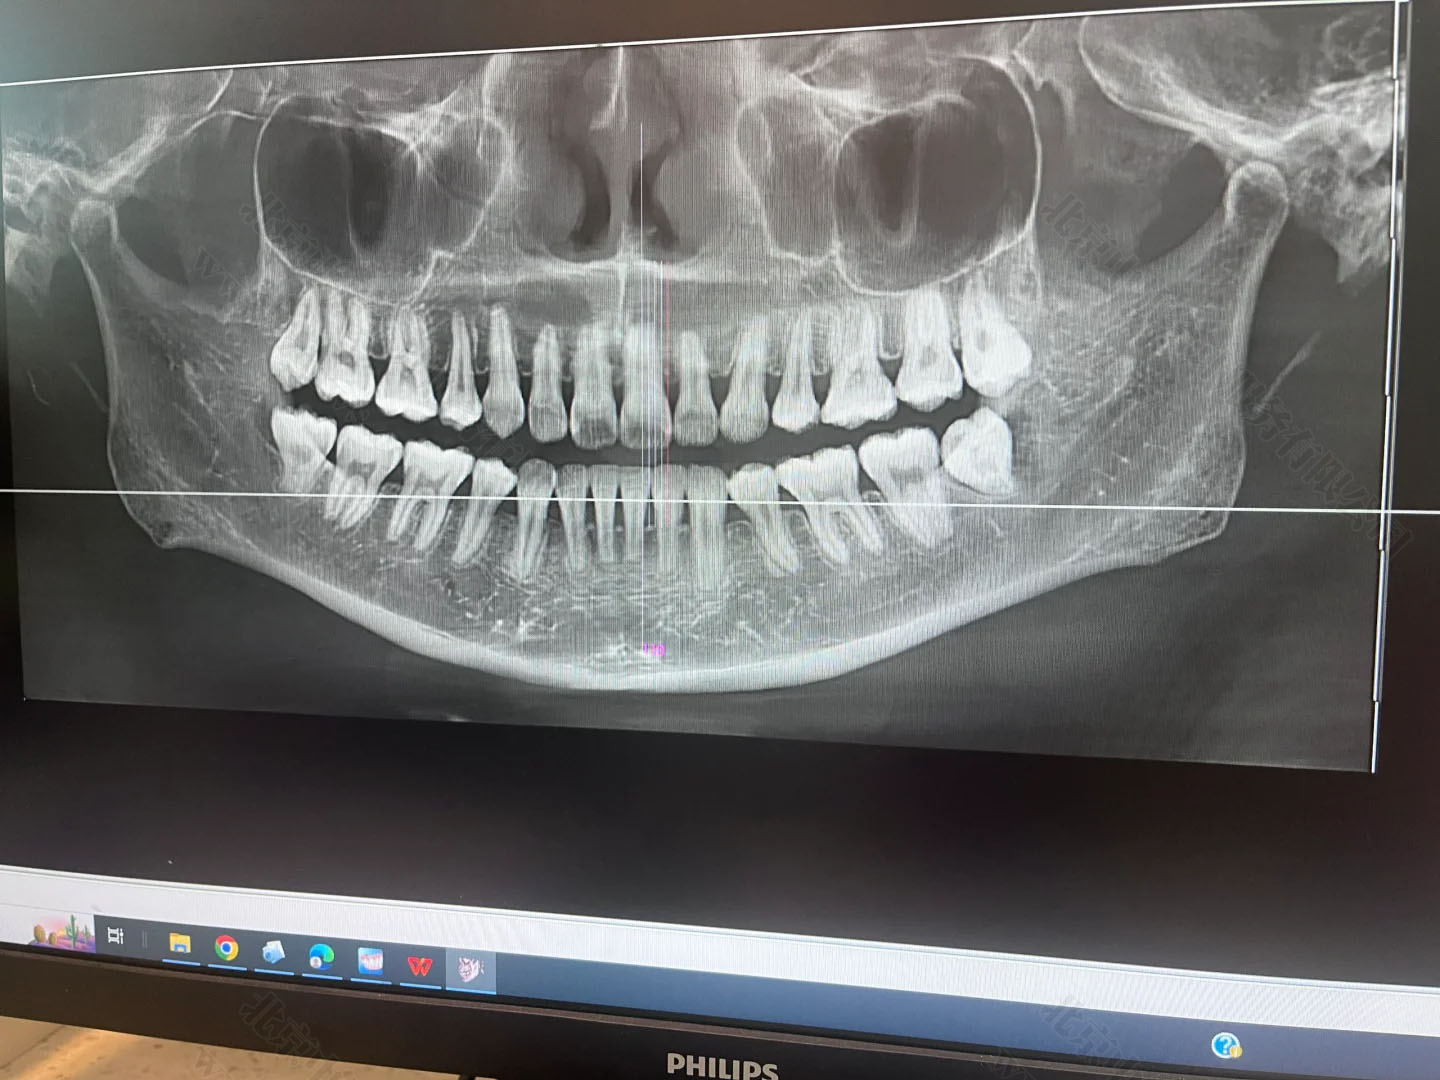

只要是裝了牙片機(jī),不管是常規(guī)拍片還是全景片,這類設(shè)備都屬于放射類診療儀器,必須先提交項(xiàng)目的放射防護(hù)預(yù)評(píng)價(jià)報(bào)告,也就是確認(rèn)這個(gè)設(shè)備對(duì)人有沒(méi)有輻射危害,能不能安裝和使用。

在施工前,這個(gè)報(bào)告必須提前交到北京市衛(wèi)生部門審核。審批通過(guò)了才能動(dòng)工裝修,否則一切都白忙活。牙片雖然是“輕放射”,但防護(hù)的流程跟CT、核磁一樣,不能跳過(guò)。

項(xiàng)目完工后也不是馬上就能拍牙片,還得請(qǐng)專業(yè)機(jī)構(gòu)做一個(gè)職業(yè)病危害控制效果評(píng)價(jià),就是看你這機(jī)器在使用過(guò)程中,周邊有沒(méi)有多余輻射,會(huì)不會(huì)對(duì)醫(yī)生、患者和旁人造成傷害。做完后,還得向衛(wèi)生部門提交設(shè)備驗(yàn)收申請(qǐng),包括檢測(cè)報(bào)告、施工資料等一整套材料。

只有經(jīng)過(guò)這道驗(yàn)收關(guān),診所才可以拿到《放射診療許可證》,正式開(kāi)展拍片業(yè)務(wù)。這個(gè)流程平均要花上兩三個(gè)月,不提前準(zhǔn)備就容易耽誤診所開(kāi)張。